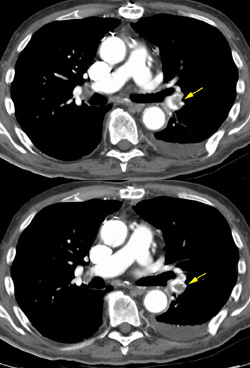

Pulmonary embolsim in a patient with left iliac vein thrombosis

By

Scott Williams

August 28, 2001